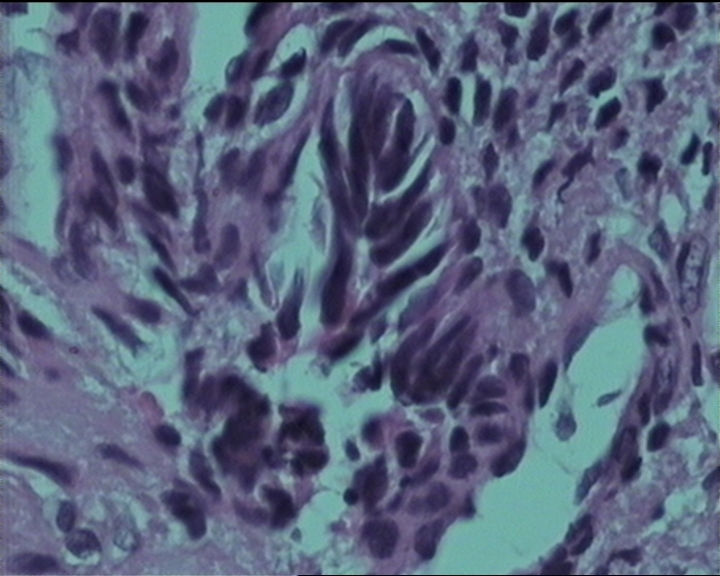

54岁女性,临床“宫颈息肉”送检;巨检:组织一块1。5*1CM,灰红。

输卵管粘膜化生

细胞及腺体均有异形,图6、11、16象有纤维间质反应,考虑高级别上皮内瘤变/原位癌,腺癌不能除外。

Sternberg病理学上诊断宫颈原位腺癌的标准是腺体的上皮去粘液分化,呈乳头状或筛网状增生,核分裂易见,这例显然达不到此标准。此例还是归入到腺上皮不典型增生为好。

It is benign. Benign endocervical polyp with tubal metaplasia.

杨老师说它是良性的,是个颈管内膜息肉伴输卵管上皮化生,良性